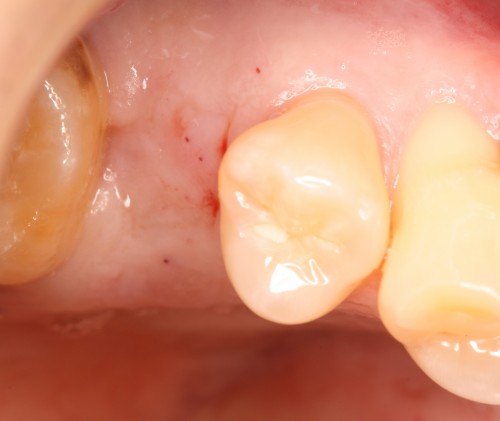

術前

被せ物の二次虫歯と根の破折